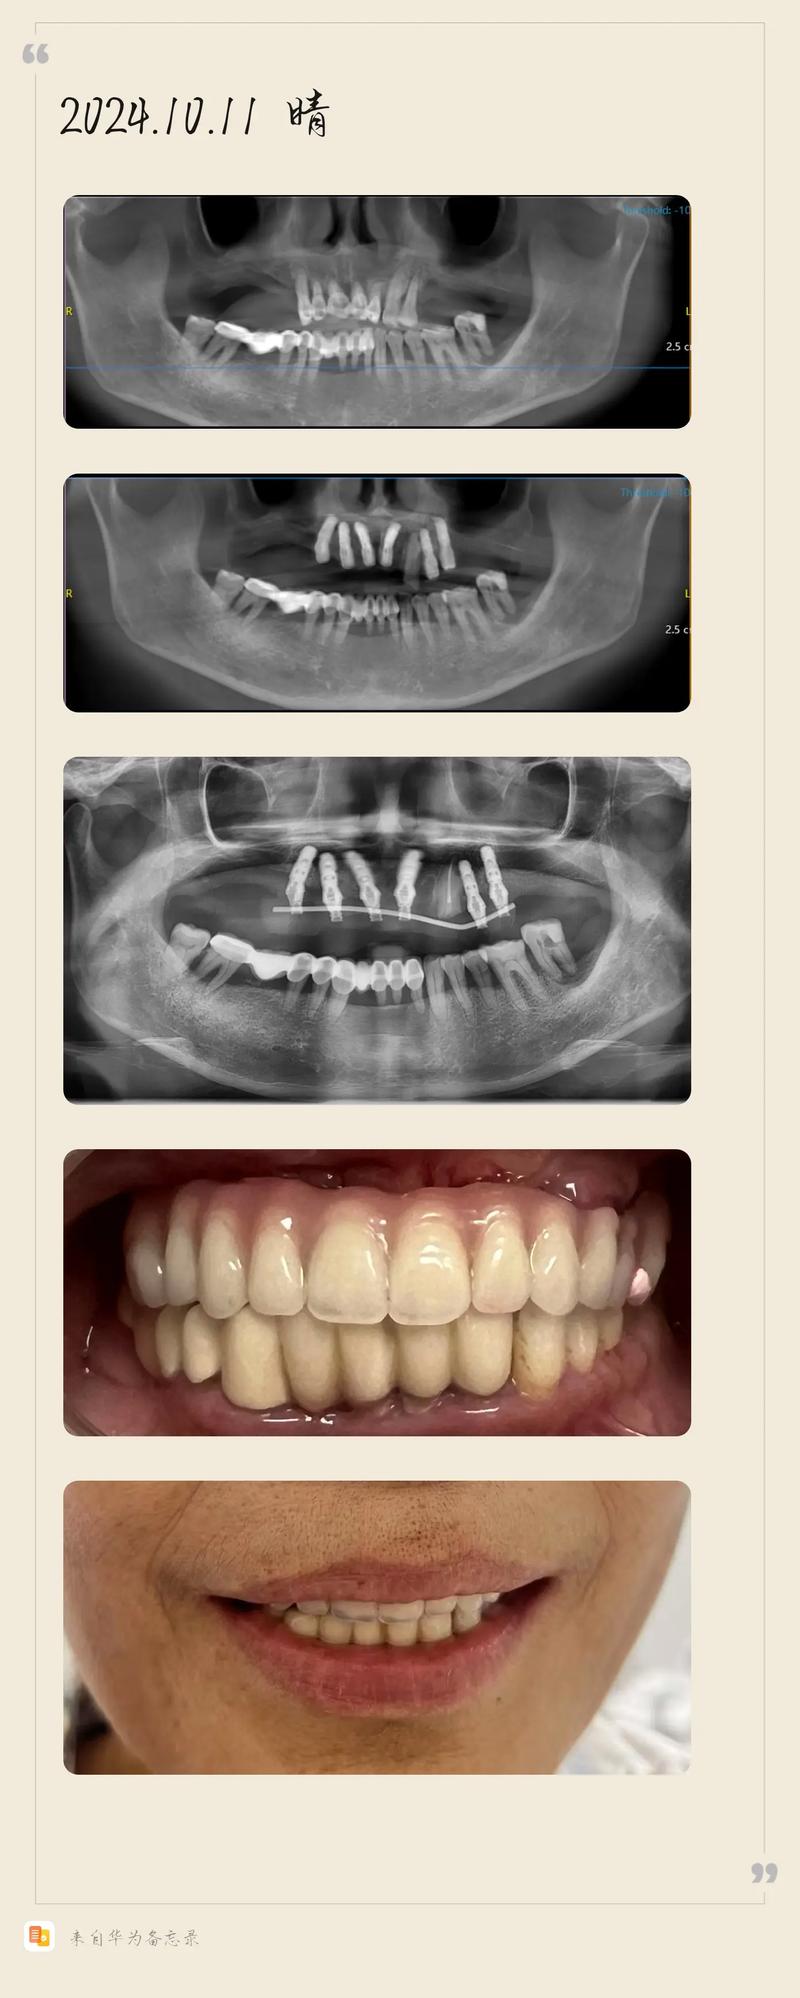

- 术前检查与设计:通过CBCT获取牙槽骨三维数据,结合口内扫描模型,利用数字化软件模拟种植位置,设计个性化种植方案和临时修复体。

- 种植体植入:在数字化导板引导下,逐级备洞后植入4-6颗种植体(根据牙槽骨条件调整),通常选择“All-on-4”或“All-on-6”技术,通过倾斜植入避开骨量不足区域,实现半口牙的即刻支撑。

- 术后随访与永久修复:术后3-6个月,待种植体与骨组织完全结合(骨结合),拆除临时修复体,更换为更美观耐用的全瓷永久牙冠。